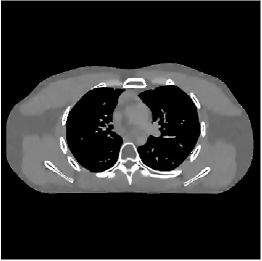

III-B3 Generalization Capability Comparisons between a “Denoising” Deep NN and the Proposed PWLS-ST- Method

This section compares the generalization capabilities between the proposed MBIR method, PWLS-ST-, and a denoising deep NN, FBPConvNet [14], that are trained from the phantom data; in particular, we tested the trained PWLS-ST- and FBPConvNet models to phantom and clinical scan data. The results in Fig. 6 show that the non-MBIR FBPConvNet method has higher overfitting risks, compared to the proposed PWLS-ST- MBIR method. When tested on clinical scan data, PWLS-ST- achieves much more accurate reconstruction, compared to FBPConvNet. See Fig. 6(b). When tested on phantom data, FBPConvNet generates more unnatural features as the number of views reduces, although it gives lower RMSE values compared to PWLS-ST-. See zoom-ins in Fig. 6(a). The FBPConvNet results above correspond to those in the recent work [16] that FBPConvNet [14] generated some unexpected structures.

| FBPConvNet (Jin et al., 2017) | Proposed PWLS-ST- | Reference | |

| % () views | |||

| (a) XCAT phantom data | |||

| (b) GE clinical data | |||